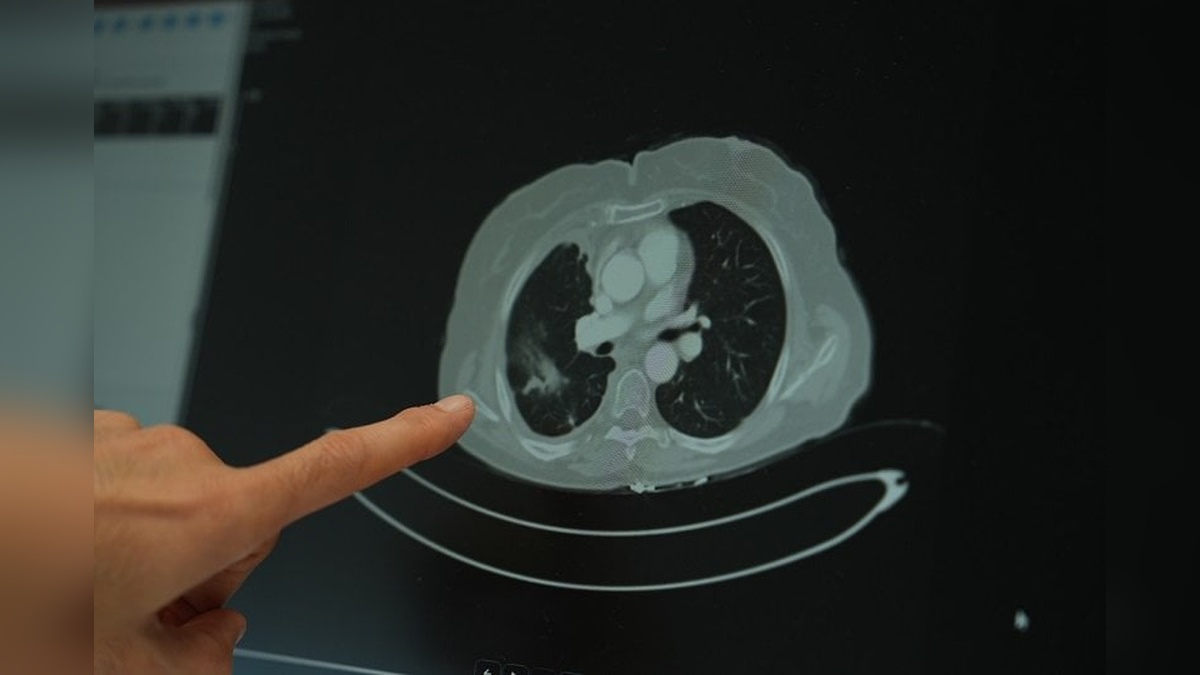

Batı tipi beslenme alışkanlıkları, et ağırlıklı diyetler ve obezitenin de kanser riskini artırdığını belirten Doç. Dr. Şimşek, sigara içen bireylerde düşük doz radyasyonla tomografi taraması önerildiğini de sözlerine ekledi. Uzun süre sigara kullananlarda akciğer kanseri riskinin yüksek olduğunu vurgulayan Doç. Dr. Şimşek, erken tanı için düşük doz radyasyonlu taramaların önemli olduğunu belirtti.